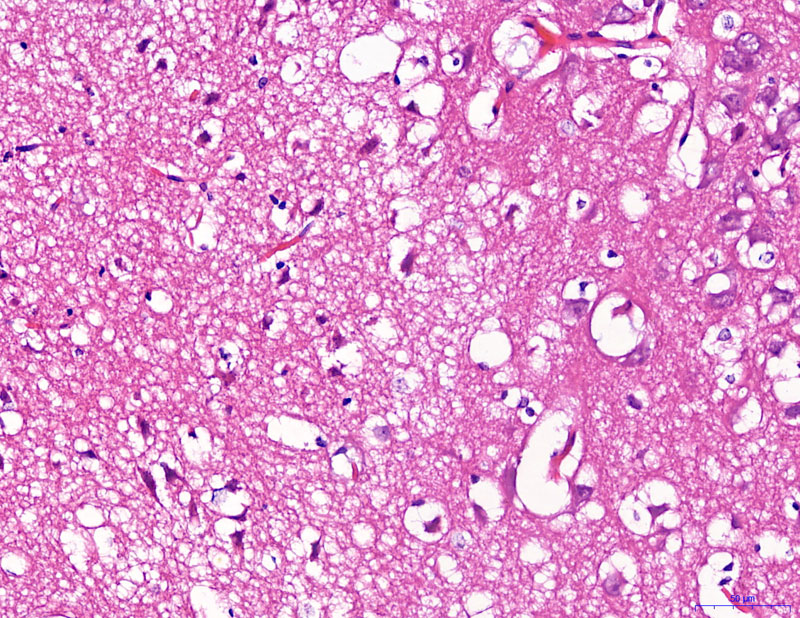

給藥-400

模型-400

正常-400